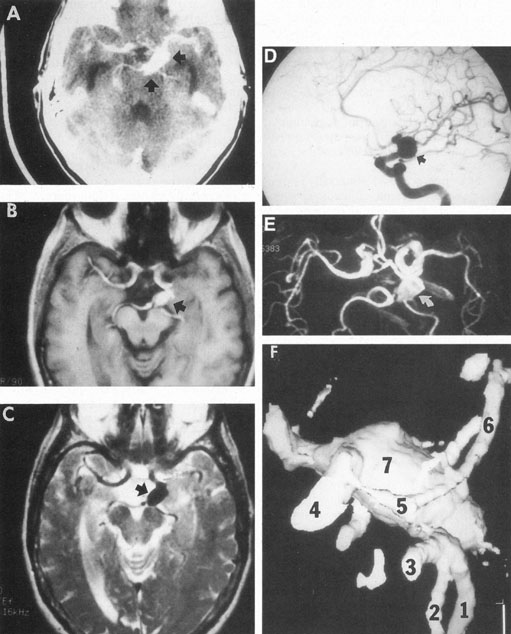

Aneurysms that primarily arise form the carotid system at the origin of the posterior communicating artery are of special interest to neurologists, neurosurgeons, and ophthalmologists because they tend to involve the oculomotor nerve. The classic presentation is sudden onset of severe unilateral frontal headache, ptosis, limitation adduction, depression and elevation of the eye, and dilated and fixed pupil. The cerebrospinal fluid is grossly bloody, and angiography is diagnostic (Fig. 5). Pain in and around the eye in the trigeminal–ophthalmic distribution is a conspicuous symptom, but sensory defects are absent. Clinical and pathologic evidence indicates that impairment of function by a contiguous aneurysm usually occurs in conjunction with hemorrhage into the oculomotor nerve that, along with sudden distortion, can produce referred pain.27

Fig. 5. Aneurysm at the junction of the internal carotid and posterior communicating arteries. A: Contrast-enhanced axial computed tomography (CT) shows a large aneurysm (arrows). Magnetic resonance imaging (MRI) studies effectively demonstrate the aneurysm. B: T1-weighted MRI with gadolinium. C: T2-weighted (arrow indicates black flow void). D: Selective internal carotid angiogram. E: Magnetic resonance angiogram (MRA; curved arrow) shows the same aneurysm. F: Helical image-intensified CT technique provides quasi-three–dimensional mold of arteries: 1. right posterior cerebral; 2. posterior superior cerebellar; 3. basilar; 4. internal carotid; 5. posterior communicating; 6. left posterior cerebral; 7. supraclinoid aneurysm, same as depicted in A through E. (Courtesy of Dr. Raphael Aponte.)

Oculomotor palsy caused by posterior communicating artery aneurysm typically shows maximal involvement of all third nerve functions. Although an individual extraocular muscle may be partially paretic, it is quite uncommon for any single extraocular muscle to be entirely spared (lateral rectus and superior oblique excluded). Relative pupillary sparing and pupillary involvement is of considerable importance in differential diagnosis. The common situation is total pupillary paralysis with ruptured or unruptured posterior communicating aneurysms that involve the third nerve, but important exceptions exist. Of course, in the clinical setting of sudden onset of a painful third-nerve palsy, with severe headache and nuchal rigidity, angiography is indicated whether or not the pupil is involved.

In approximately one-half of patients with ruptured posterior communicating artery aneurysms, third-nerve palsy develops either immediately or within a day. Aneurysms can cause ipsilateral frontal headache and third-nerve palsy by compression before they actually rupture. Approximately 70% of symptomatic but unruptured, aneurysms show a third-nerve palsy, and by far the most common location is at the origin of the posterior communicating artery.12 The incidence of oculomotor palsy with posterior communicating artery aneurysms varies from 34% to 56%.28